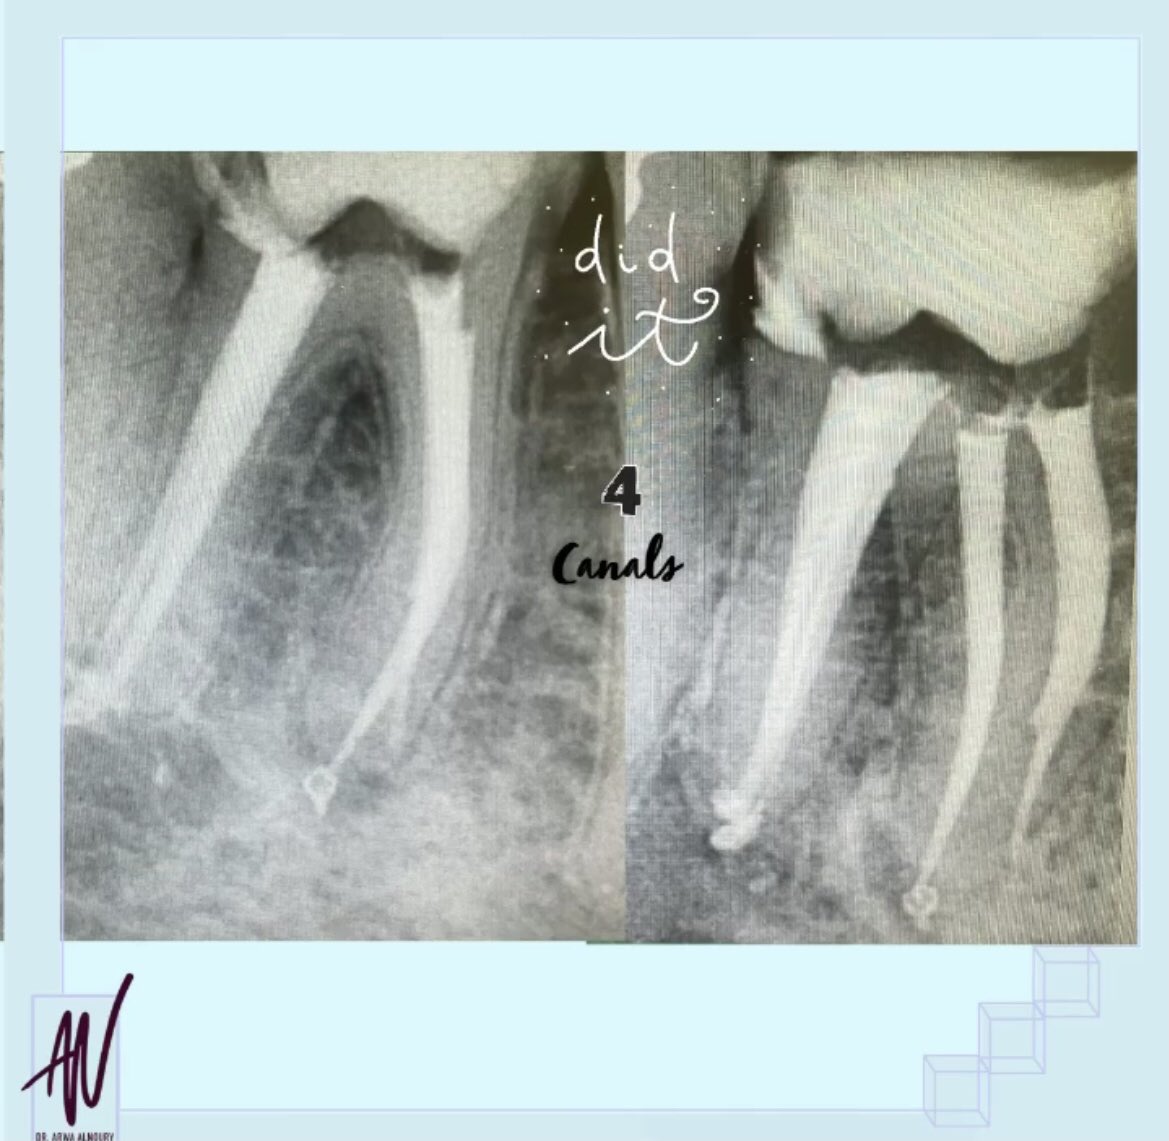

نعم هذه الصوره قبل وبعد ولكن..... شوفو معي خطوة بخطوة كيف قدرنا نحافظ على هذا السن🦷❤️